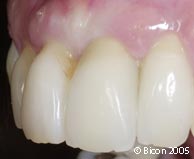

12. | 石膏模型上的一体化基台冠。 |

13. | 上颌左侧切牙的一体化基台冠。 |

14. | 上颌左中切牙的一体化基台冠。 |